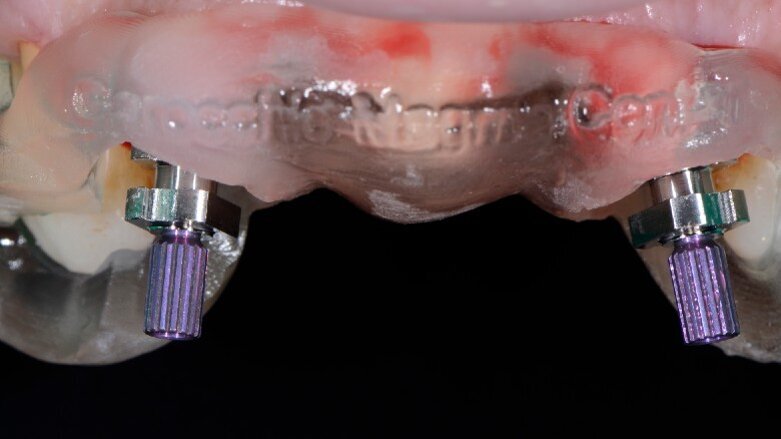

Alloggiamo la dima protesica (Fig. 33), e blocchiamo i transfert con della resina trasparente (tecnica DIL) (Figg. 34, 35). In questo modo possiamo far riposare il paziente in studio dopo appena 35 minuti dall’inizio dell’intervento. La dima protesica, infatti (Fig. 36) con i transfert inseriti viene completata con l’unione degli analoghi ai transfert (Fig. 37). L’insieme così composto viene riadattato sul modello master digitale iniziale (Figg. 38-40) sul quale era stata costruita sia la dima chirurgica che la dima protesica come anche il provvisorio. Gli analoghi vengono bloccati sul modello con resina trasparente (Figg. 41-43). Alloggiamo il provvisorio sul modello master digitale così ottenuto (Figg. 44, 45).

Fig. 34 - Transfert bloccati con resina trasparente.

Fig. 35 - Rimozione dima protesica.

Fig. 36 - Dima protesica e transfert bloccati.

Fig. 37 - Dima protesica e transfert bloccati.